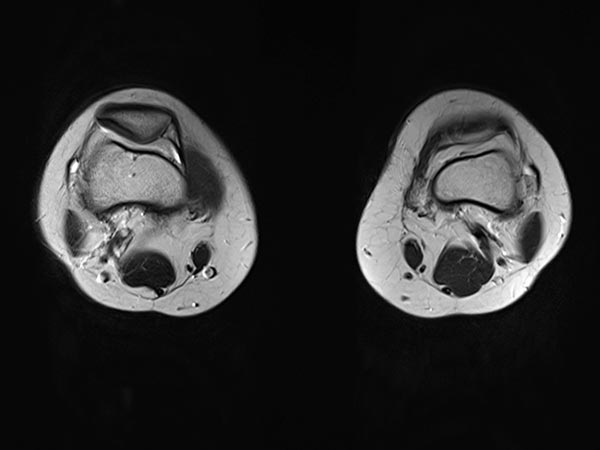

Die vollständig verschlossene venöse Malformation, die atypischerweise deutliche arteriovenöse Fisteln enthielt, konnte nach erfolgreicher Embolisation und Sklerosierungsbehandlung mit vollständigem Verschluss erfolgreich offen reseziert werden. Die axiale T2-gewichtete MRT zeigt die Vollständigkeit der Resektion ohne eine verbliebene Läsion.

Die vollständig verschlossene venöse Malformation, die atypischerweise deutliche arteriovenöse Fisteln enthielt, konnte nach erfolgreicher Embolisation und Sklerosierungsbehandlung nach vollständigem Verschluss erfolgreich offen reseziert werden. Die Patientin ist seither asymptomatisch (3 Jahre, 4 Monate).